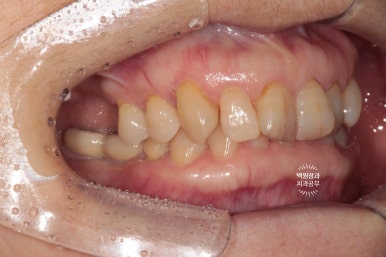

옆에서 보아도 너~무 잘 보이는 앞니 세로 금. 치아의 끝단에는 충치로 생각되는 어둑함이 자리잡고 있었고..

사진을 보시면 아시겠지만, 오른쪽 위 어금니 두개가 없으신 상태였습니다.